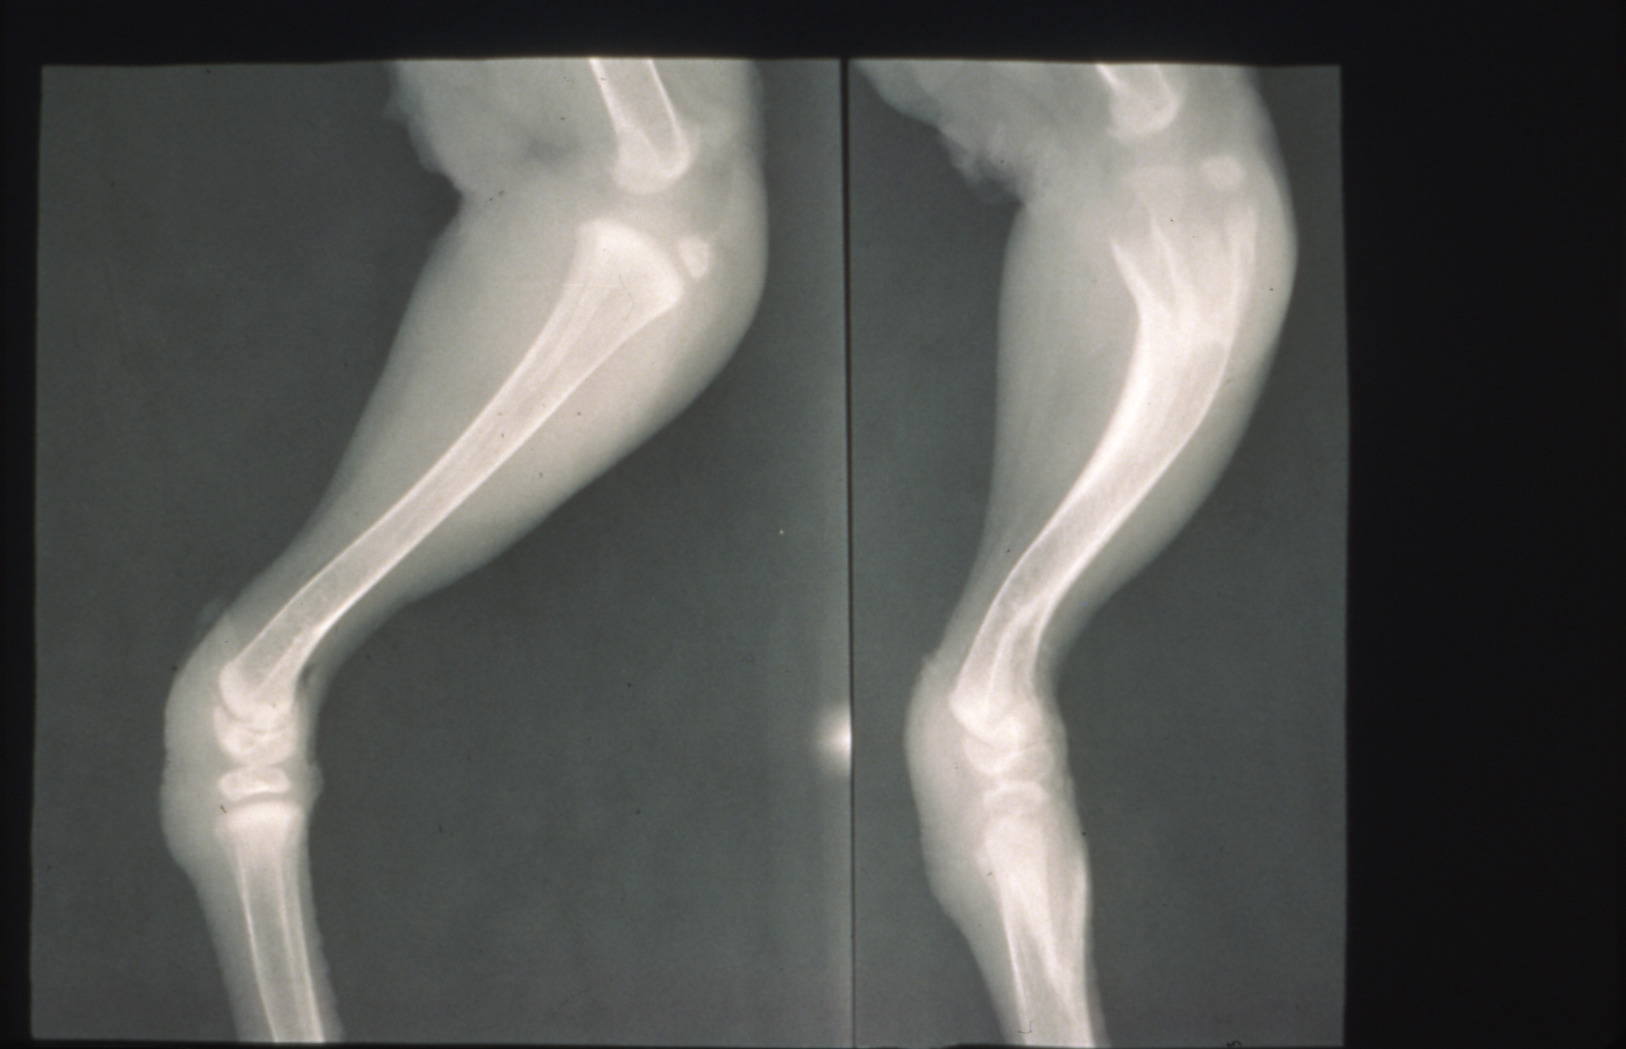

Tibial dyschondroplasia in domestic poultry (slide study set no. 6) Item Info

Tibial dyschondroplasia in domestic poultry (slide study set no. 6)

Avian medicine Poultry--Diseases Tibia

Slide Study Set #6, Tibial Dyschondroplasia, 2 sets (includes 34 color slides), 1975